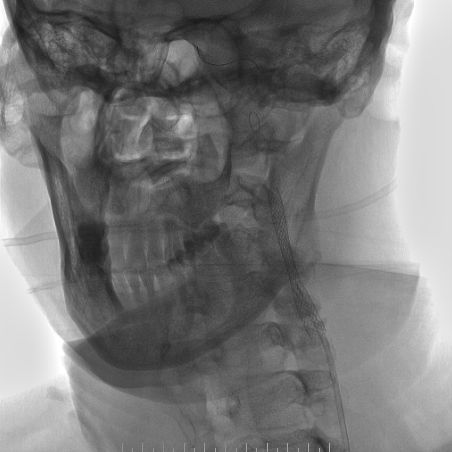

手术过程

-- 右侧桡动脉穿刺置入7F 泰尔茂薄壁鞘,波科7F0.081导引导管同轴5F 125cm SimmonsII导管在0.035导丝引导下引至左侧颈总动脉。